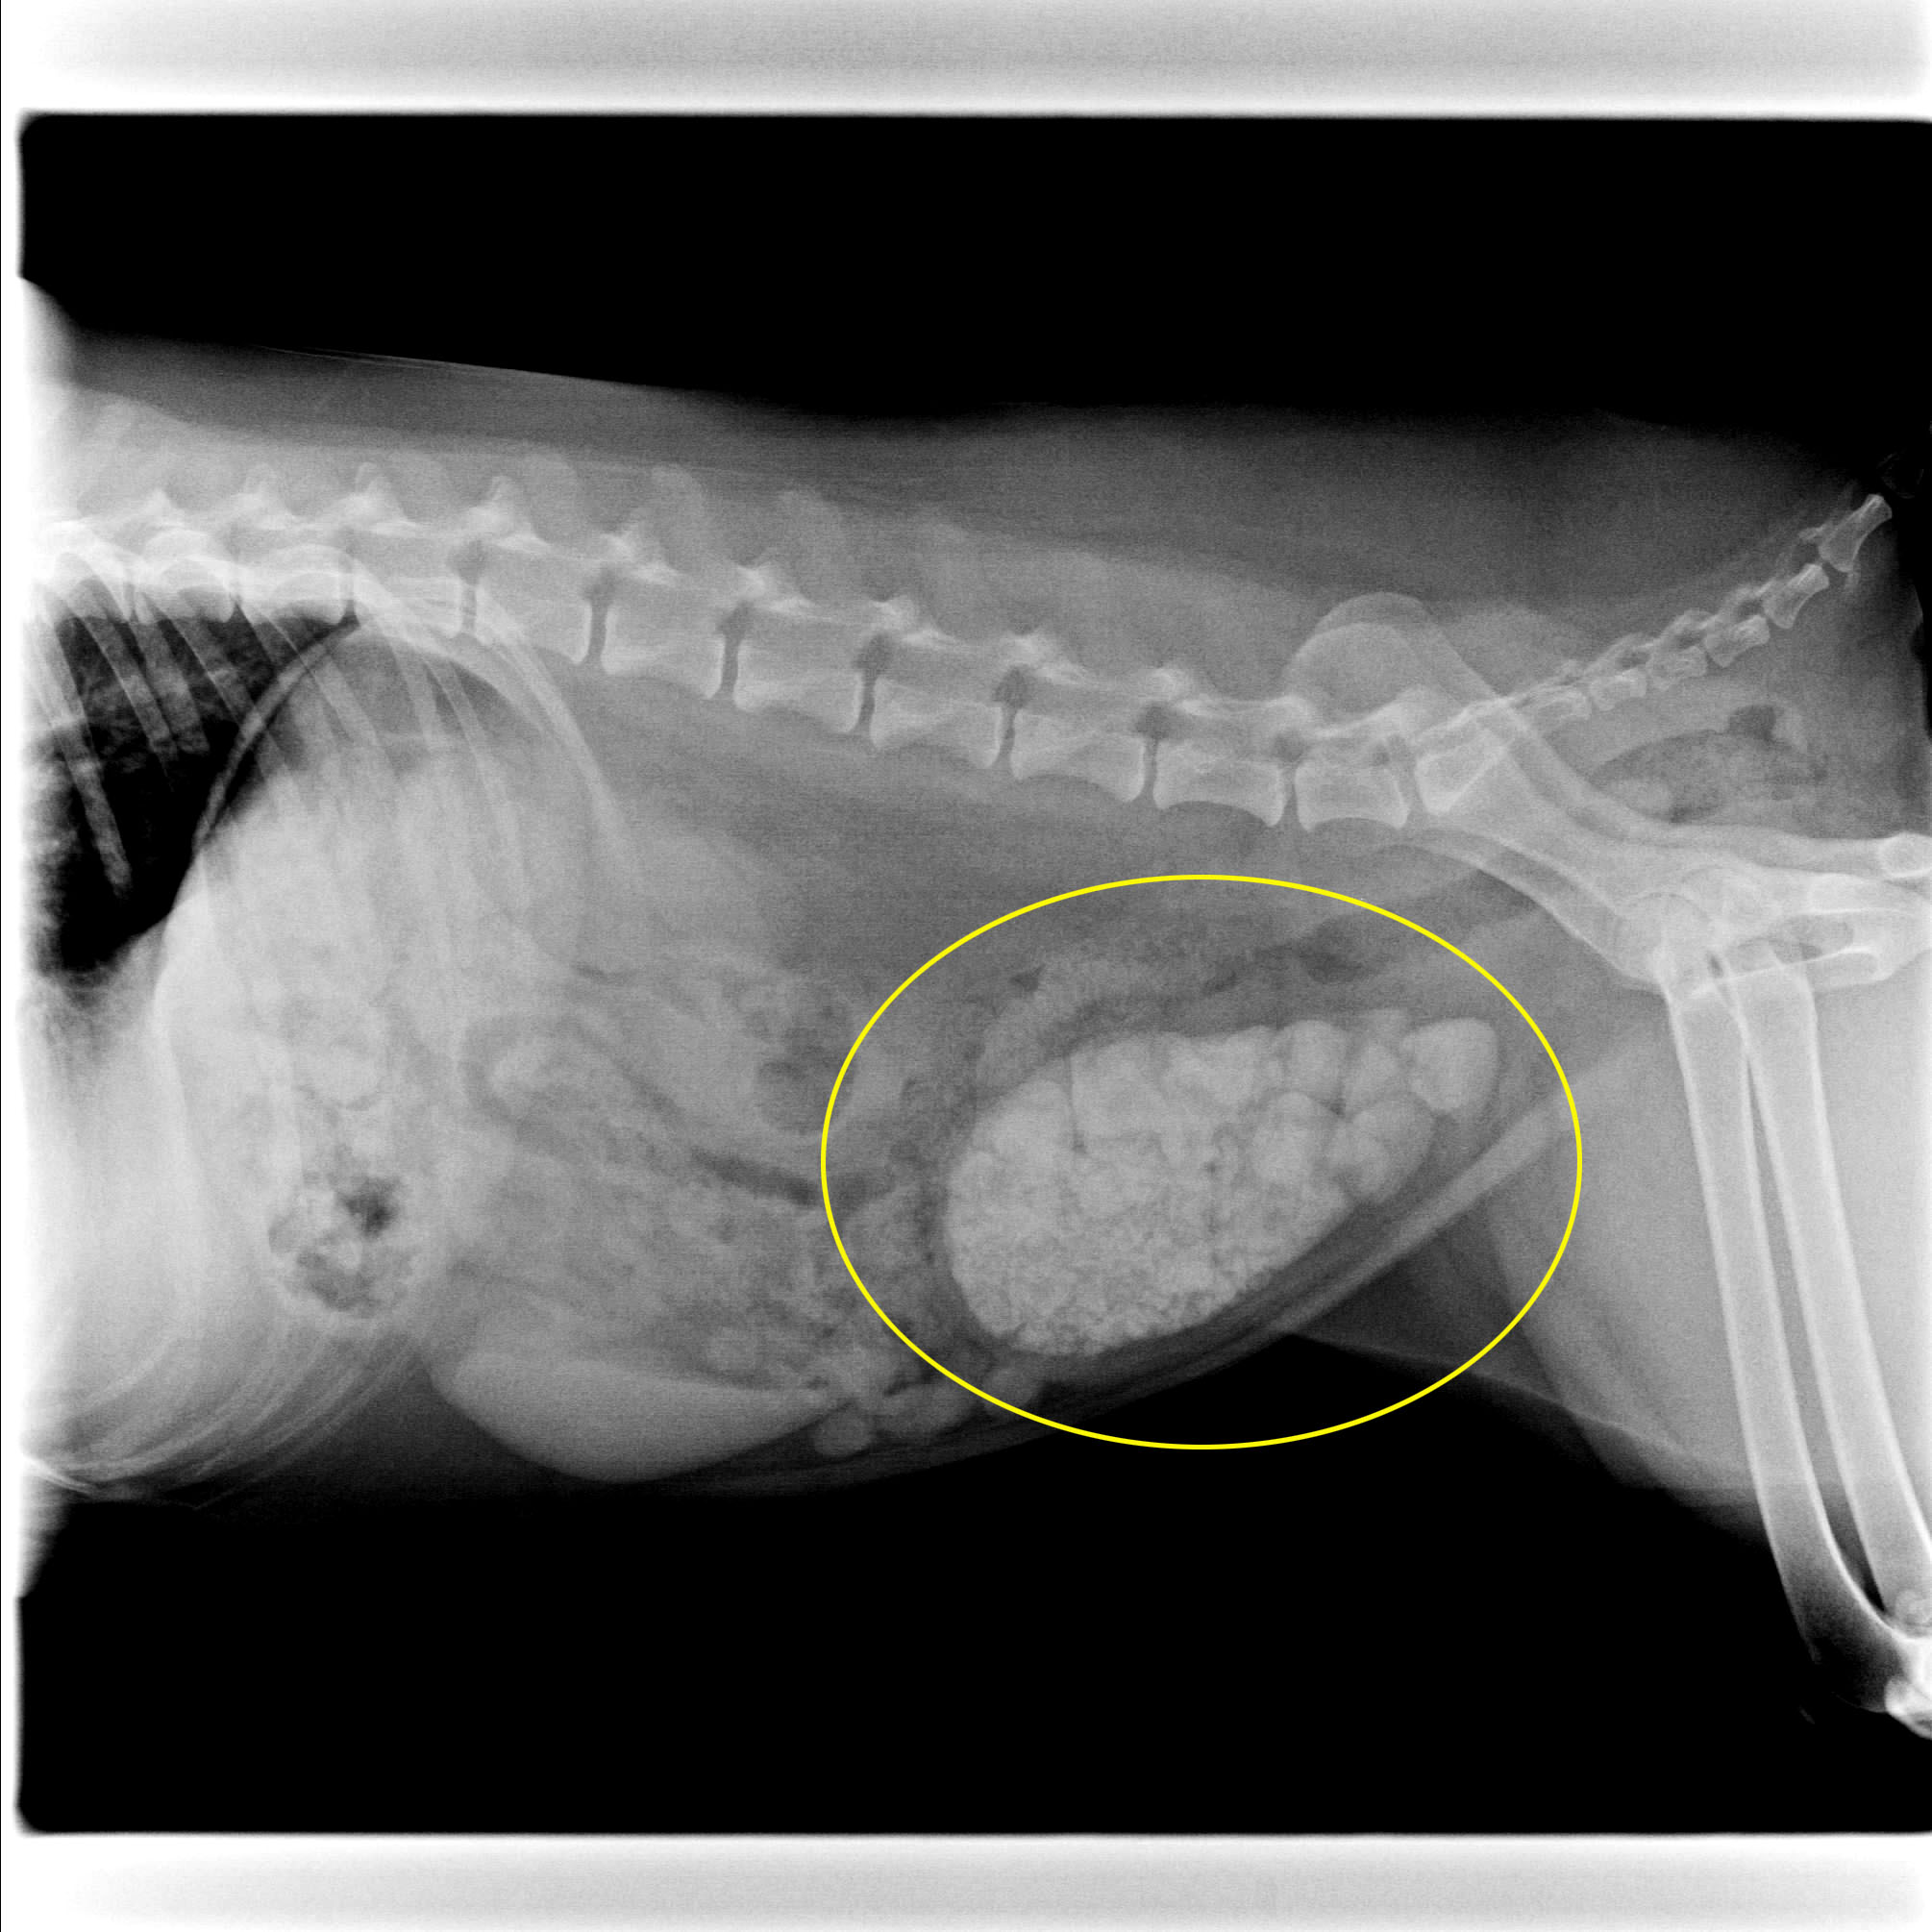

犬 膀胱結石・尿道結石 チワワ 10歳11ヶ月齢 去勢オス 71kg 頻尿と血尿、排尿障害を主訴に来院 腹部と陰茎の触診検査にて結石症が疑われたため、 レントゲン検査を行い、膀胱結石および尿道結石、腎臓結石と診断した 尿道内にぎっしりとつまった結石は、カテーテルにて膀胱内に押し戻し、膀胱切開にて膀胱結石を摘出した 腎臓結石はに対する外科処置は、腎臓. 犬の膀胱結石 更新日時: ミニチュアダックスフンド、オス (去勢)、11歳 《主訴》血尿、排尿しづらい (少量ずつしか出ない) 《検査》①腹部レントゲン検査 膀胱に結石と思われる不透過性陰影を多数確認 ②腹部超音波検査 膀胱内に結石と思われるシャドーを引く高エコー物を多数確認 ③尿.

一例犬膀胱结石的治疗总结 参考网

一例犬膀胱结石的治疗总结 参考网

一例犬膀胱结石诊疗报告

一例犬膀胱结石的诊断与治疗